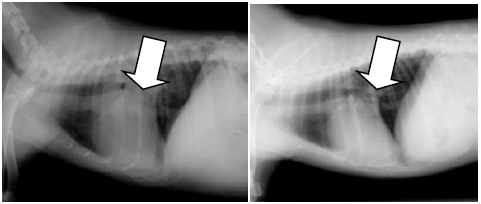

この子の胸を横から撮影したレントゲン写真です。

左が手術前、右が手術後です。

矢印で示された心臓のサイズが目に見えて小さくなっています。